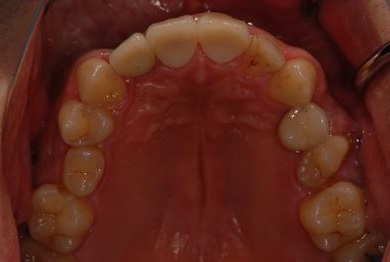

インプラントの症例写真 IMPLANT

抜歯即日スピードインプラント治療

| 性別/年齢 | 男性 / 36歳 | ||||||||||||||||||||||||||||||||

| 主訴 | 歯が折れているので、インプラントにしたい。 | ||||||||||||||||||||||||||||||||

| 治療方針 | 抜歯と同時にインプラント埋入を行い、治療期間を短縮する。 | ||||||||||||||||||||||||||||||||

| 治療内容 | インプラント2本(抜歯即日インプラント治療)、ジルコニアフレームオールセラミッククラウン1本、オールセラミッククラウン2本(セラミック用土台2本)、メタルボンドセラミッククラウン1本 | ||||||||||||||||||||||||||||||||